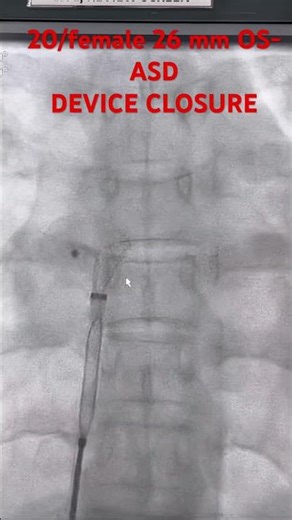

ASD Device Closure - ASD Device Closure

in Cath Lab - Toe for